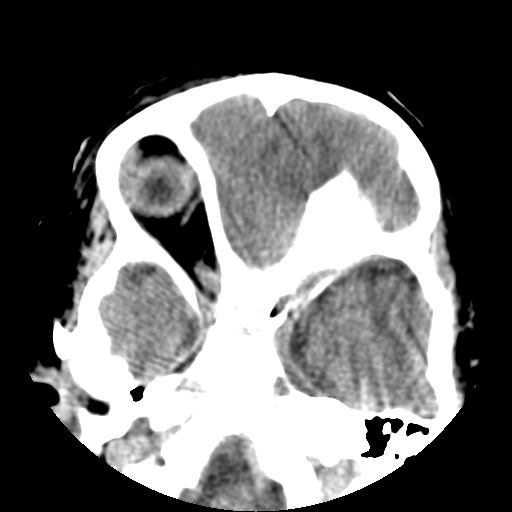

以下是引用深泽交通医院在2009-10-16 8:25:00的发言:[br]右眼环出血伴异物

以下是引用卜一在2009-10-16 15:01:00的发言:[br]右眼球挫裂伤伴异物!

以下是引用拾荒者在2009-10-17 18:38:00的发言:[br]鼻面部皮下积气,右侧睑缘及眼球壁高密度异物影,左侧眼球壁晶状体内侧缘处是圆形低密度影。低密度异物?应提请眼科医生注意。